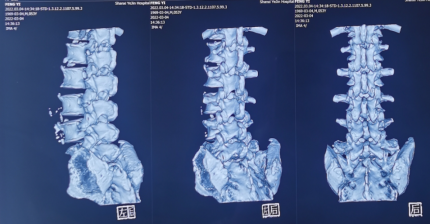

来到陕西冶金医院神经脊柱科后,由张少华主任、熊东主任接诊,经过各项检查后发现他在腰3/4、腰4/5、腰5/骶1都有不同程度的突出,尤其是在腰4/5突出非常严重。鉴于曹先生主要的症状表现和影像学等检查结合,判断腰4/5为主要责任节段,并建议尽快进行微创手术,给神经进行解压。

内镜下成功取出突出的椎间盘

由于曹先生工作繁忙,家里又有老人、孩子需要照顾,自己抽不出特别长的假期来休养,我们建议他进行椎间孔镜手术,术后恢复快,当天可下地活动,不需要特别照顾,自己就能自理,曹先生这才放下心来,接受手术。

熊东主任为曹先生成功进行椎间孔镜手术后,他的症状得到了很快的缓解,术后第二天就戴着腰围在病房自如活动了。不久后,曹先生就回归正常生活、工作了。